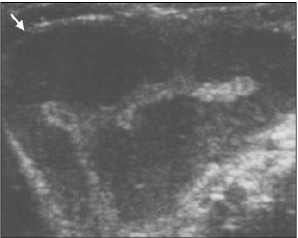

“Criança, dois anos, é submetida ao ultrassom para investigação de quadro de vômitos, fezes muco-sanguinolentas e

massa abdominal palpável.” O ultrassom abdominal chama atenção em determinado momento pelo achado a seguir

(seta branca):